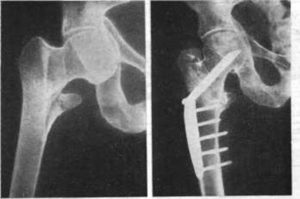

Рис. 2 Рентгенограммы тазобедренного сустава. а. межвертельный перелом бедренной кости; б. чрезвертельный перелом бедренной кости.

Межветрельные и черзвертельные переломы бедренной кости бывают стабильными и нестабильными. В первом случае репозиция не вызывает затруднений, поскольку кортикальный слой кости поврежден незначительно. Во второй ситуации лечение продолжительное и сложное.